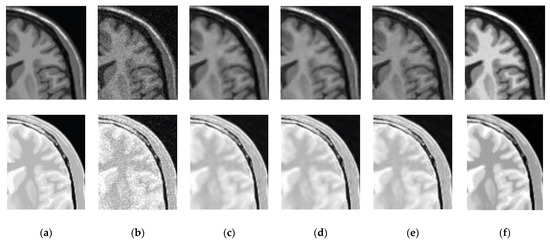

3.2. Comparative Performance in Standard Images